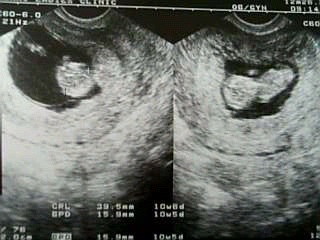

10weeks6days

いままで計算していた予定日は7月16日。

これは最終月経が始まった日(0週0日が10月9日)から計算したもの。

今日、病院で計算された予定日は7月18日(0週0日が10日11日)。

現在のベビーの大きさから計られた日にちデス。